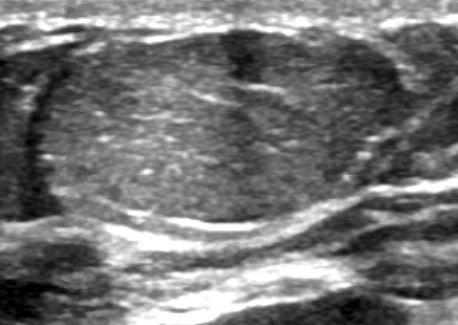

- Well circumscribed, homogenous, hyperdense or isodense, solid mass (Clin Imaging 2018;51:300)

- Typically devoid of calcifications

- Hypoechoic on ultrasound, may have posterior enhancement

- May be multilobulated

- Bilateral and multicentric tumors rare (Mod Pathol 1996;9:786, Int J Surg Pathol 2018;26:242)

Radiology images